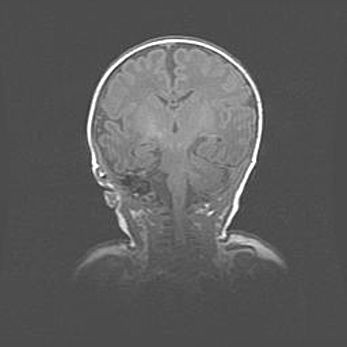

Ниже представлена  галерея МРТ снимков, полученных с применением LMT неонатальных матричных РЧ катушек. Также каждая группа МРТ снимков сопровождается информацией о пациенте (диагноз, возраст, вес, пол, срок гестации) и краткой сопроводительной расшифровкой диагноза.

Сообщающаяся гидроцефалия. Кистозная энцефаломаляция головного мозга.

Возраст: 3 месяца 4 дня

Вес: 3100 г

Пол: женский

Окружность головы: 34 см

Срок гестации: 31 неделя

Кистозная энцефаломаляция головного мозга - одна из форм поражения головного мозга в детском возрасте. Характеризуется возникновением множественных и распространённых кист в коре, белом веществе и подкорковых образованиях головного мозга у плодов, новорождённых и детей раннего возраста. Развитие кистозной энцефаломаляции связано с внутриутробной асфиксией и гипотонией, родовой травмой, тромбозом синусов, пороками развития сосудов, инфекциями, сепсисом и другими причинами. Наиболее значимые инфекционные агенты: вирусы простого герпеса, цитомегалии, краснухи, токсоплазмы, энтеробактерии, золотистый стафилококк и другие.